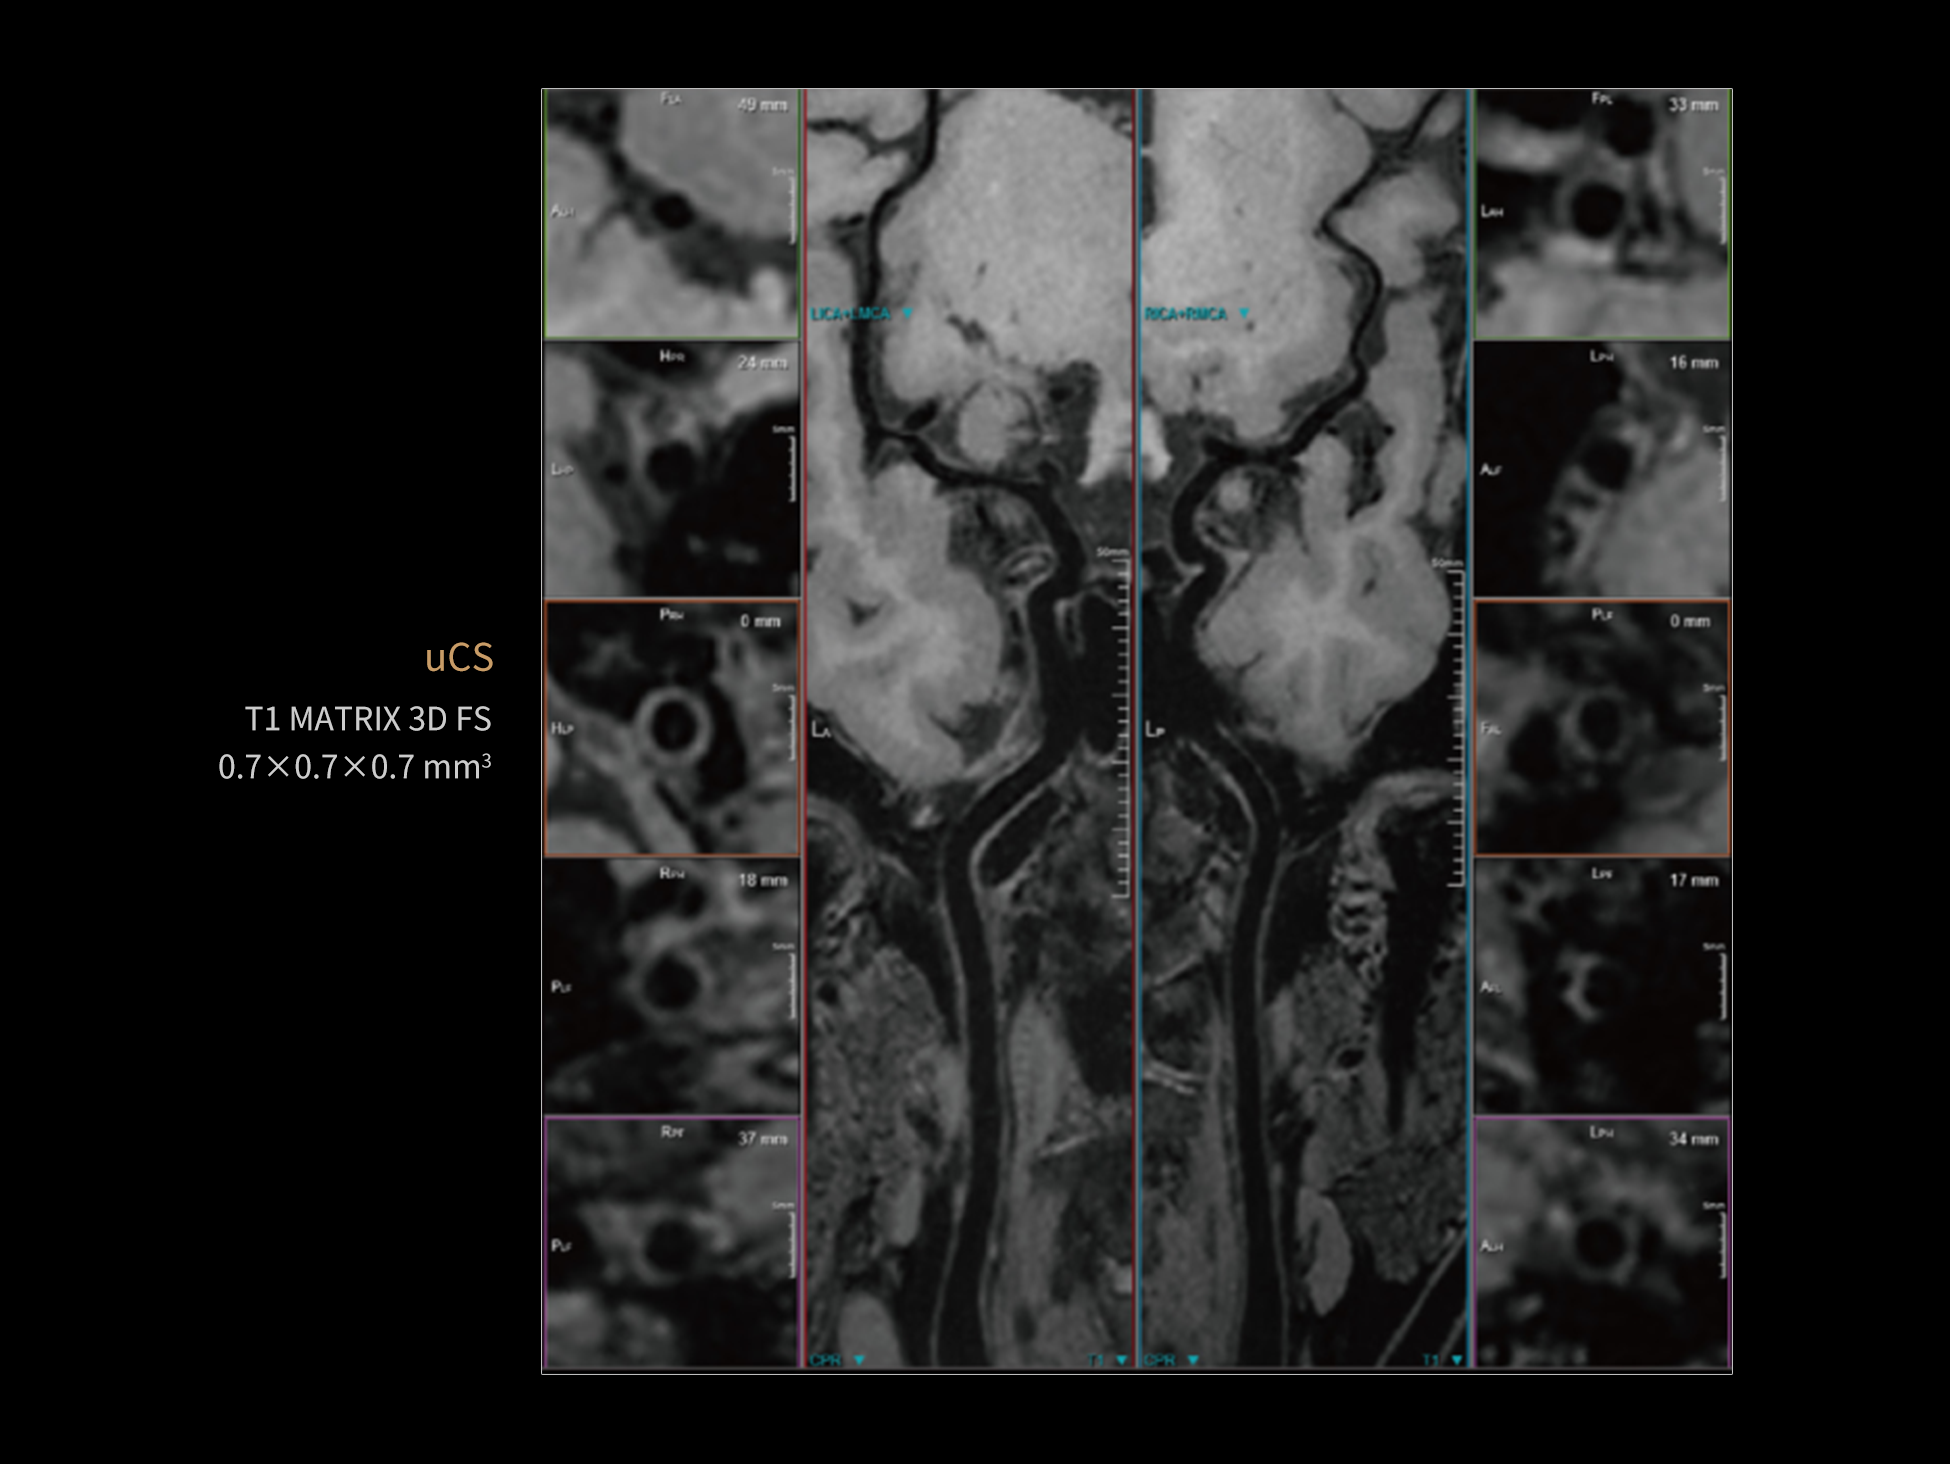

uCS 3D acquires continuous image data in an extremely short amount of time through a single scan. It allows for the reconstruction of images on any desired plane, including transverse, sagittal, coronal, and any oblique planes. uCS 3D enables more accurate identification of fine structures and detection of lesions, providing confidence in diagnosis.

High resolution, improved signal-to-noise ratio (SNR), and enhanced imaging speed, collectively contribute to significant clinical value in the prevention, diagnosis, and prognosis evaluation of cerebrovascular disease.

Supports the automatic extraction of blood vessel centerlines, facilitates automatic vessel wall analysis, enables calculation of lumen stenosis rates, and allows for seamless integration of sending, editing, and printing of structured reports.

| Accurate extraction of vessel centerlines and vessel contours

| Automated detection of abnormal areas in the target vessels and obstruction analysis

| Significant optimization of workflow

Providing a contrast-agent-free option, it minimizes patient discomfort and allergic reaction risks while delivering clear and detailed vascular anatomy information, enhancing safety and convenience in clinical diagnosis.